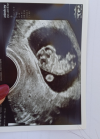

Cześć, ja juz po wizycie wg usg 9t2d, fhr178. Mam juz skierowanie na prenatalne i w końcu kartę ciąży 🥰

• Messenger_creation_64953366-DC5F-493D-8B5F-CF6178F2E2FF.png

Messenger_creation_64953366-DC5F-493D-8B5F-CF6178F2E2FF.png

414,8 KB · Wyświetleń: 75